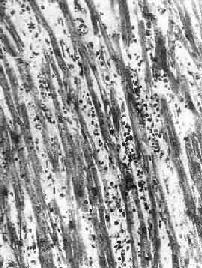

图8-41 病毒性心肌炎 心肌间质内有弥漫性淋巴细胞及组织细胞浸润

一、病毒性心肌炎病毒性心肌炎(viral myocarditis)颇为常见,是由亲心肌病毒引起的原发性心肌炎症,常累及心包,引起心包心肌炎。事实上,所谓特发性心肌炎极可能是因病毒感染引起。 【病因和发病机制】 可引起心肌炎的病毒种类颇多,其中最常见的是柯萨奇(Coxsackie)病毒、ECHO病毒(即人肠孤病毒)、风疹病毒、流行性感冒病毒、腮腺炎病毒等。由于在妊娠最初3个月内感染柯萨奇病毒和风疹病毒时可引起胎儿的先天性心脏畸形,因此,这两种病毒占有特别重要的地位。人类的心肌炎以柯萨奇病毒B组感染最为常见。一般而言,亲心肌病毒可直接破坏心肌细胞,但也可通过T细胞介导的免疫反应间接地破坏心肌细胞。由于此类病毒衣壳的糖蛋白分子结构与心肌细胞膜的糖蛋白相似,故在感染后,机体所产生的抗体(激活补体的抗体及中和病毒的抗体)既针对病毒,亦针对心肌细胞。因此,当细胞毒性T细胞被致敏后,即可破坏被病毒感染的心肌细胞。 【病变】 本病病变依患者年龄不同而有所不同。妊娠最初3个月的胎儿感染风疹病毒时,可引起心内膜下心肌的无反应性心肌细胞坏死。在妊娠后期,胎儿感染柯萨奇病毒时则可引起全心炎,大多伴有心骨膜纤维弹性组织增生。初生儿的病毒性心肌炎可见到心肌细胞坏死及粒细胞浸润。其后,代之以巨噬细胞、淋巴细胞、浆细胞浸润及肉芽组织形成(图8-41)。在成人,多累及心房后壁、室间隔及心尖区,有时可累及传导系统。镜下,主要病变为坏死性心肌炎。晚期,可见到明显的心肌间质纤维化,伴有代偿性心肌肥大及心腔扩张(充血性心肌病)。